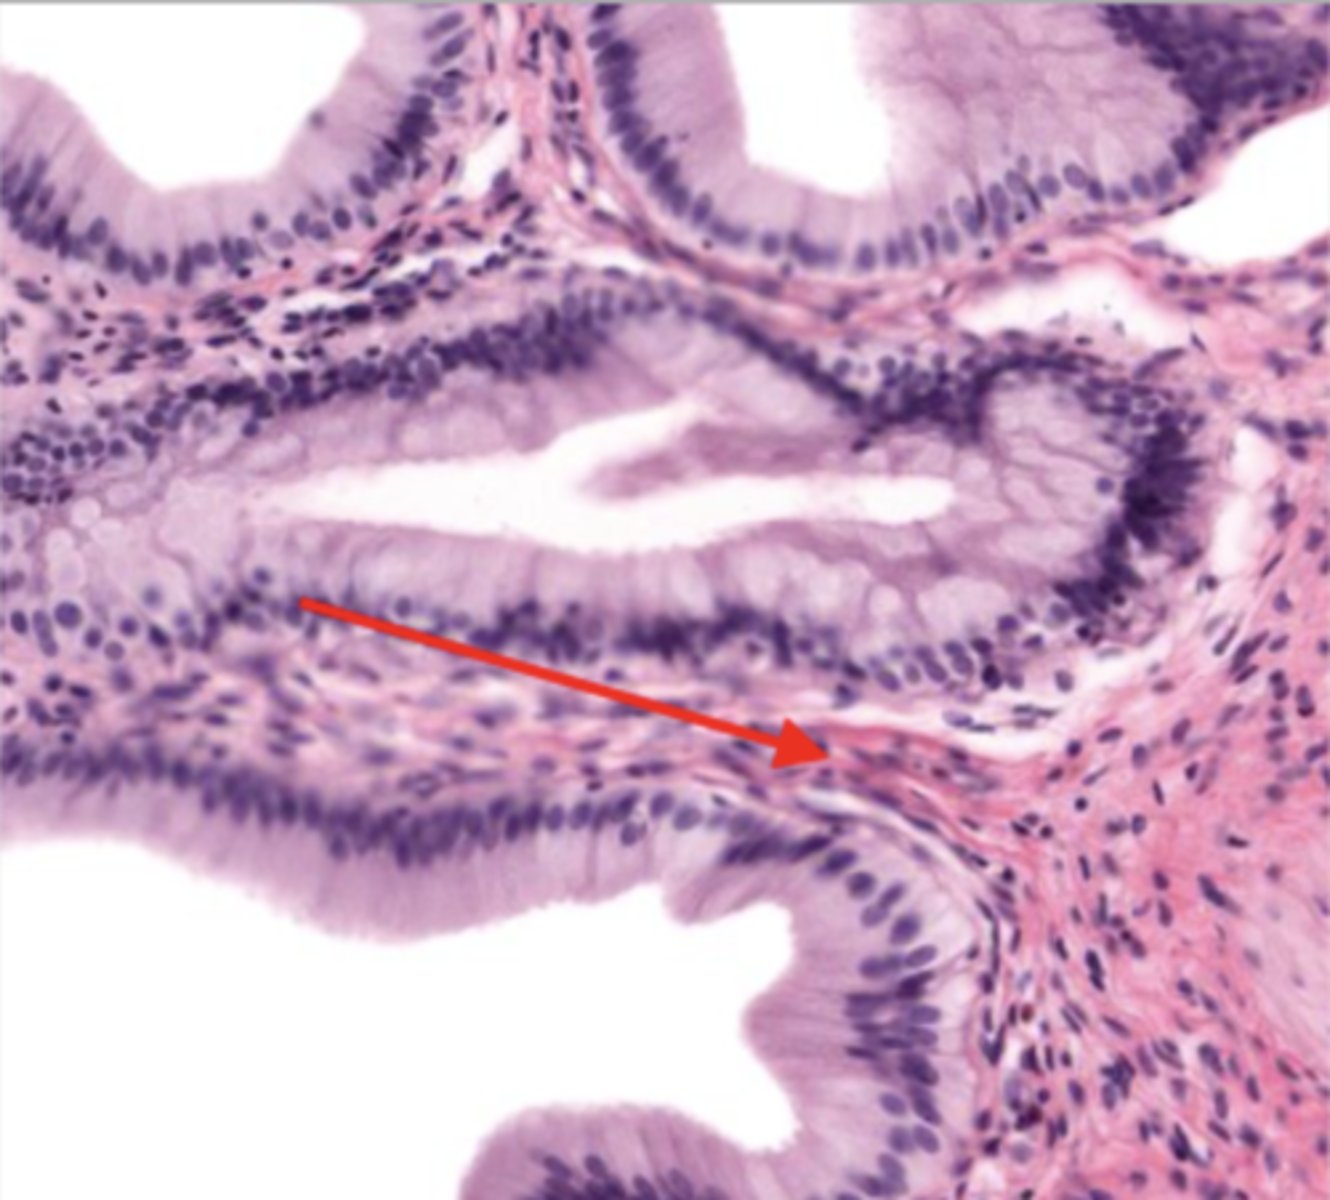

villi (jejunum)

intestinal crypts (jejunum)

mucosa (jejunum)

mucosal epithelium (jejunum)

lamina propria (jejunum)

muscularis mucosa (jejunum)